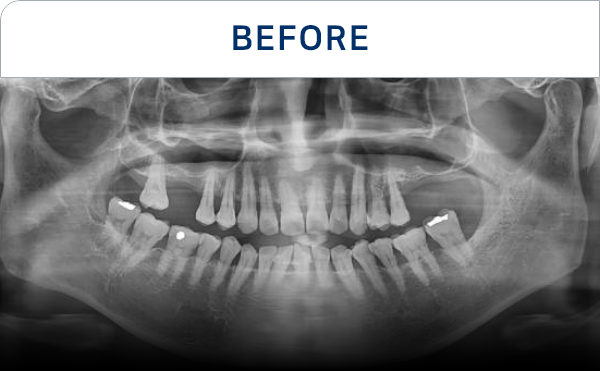

전후가 명확한 결과, 그 결과가

곧 신길플란트치과의 신뢰입니다.